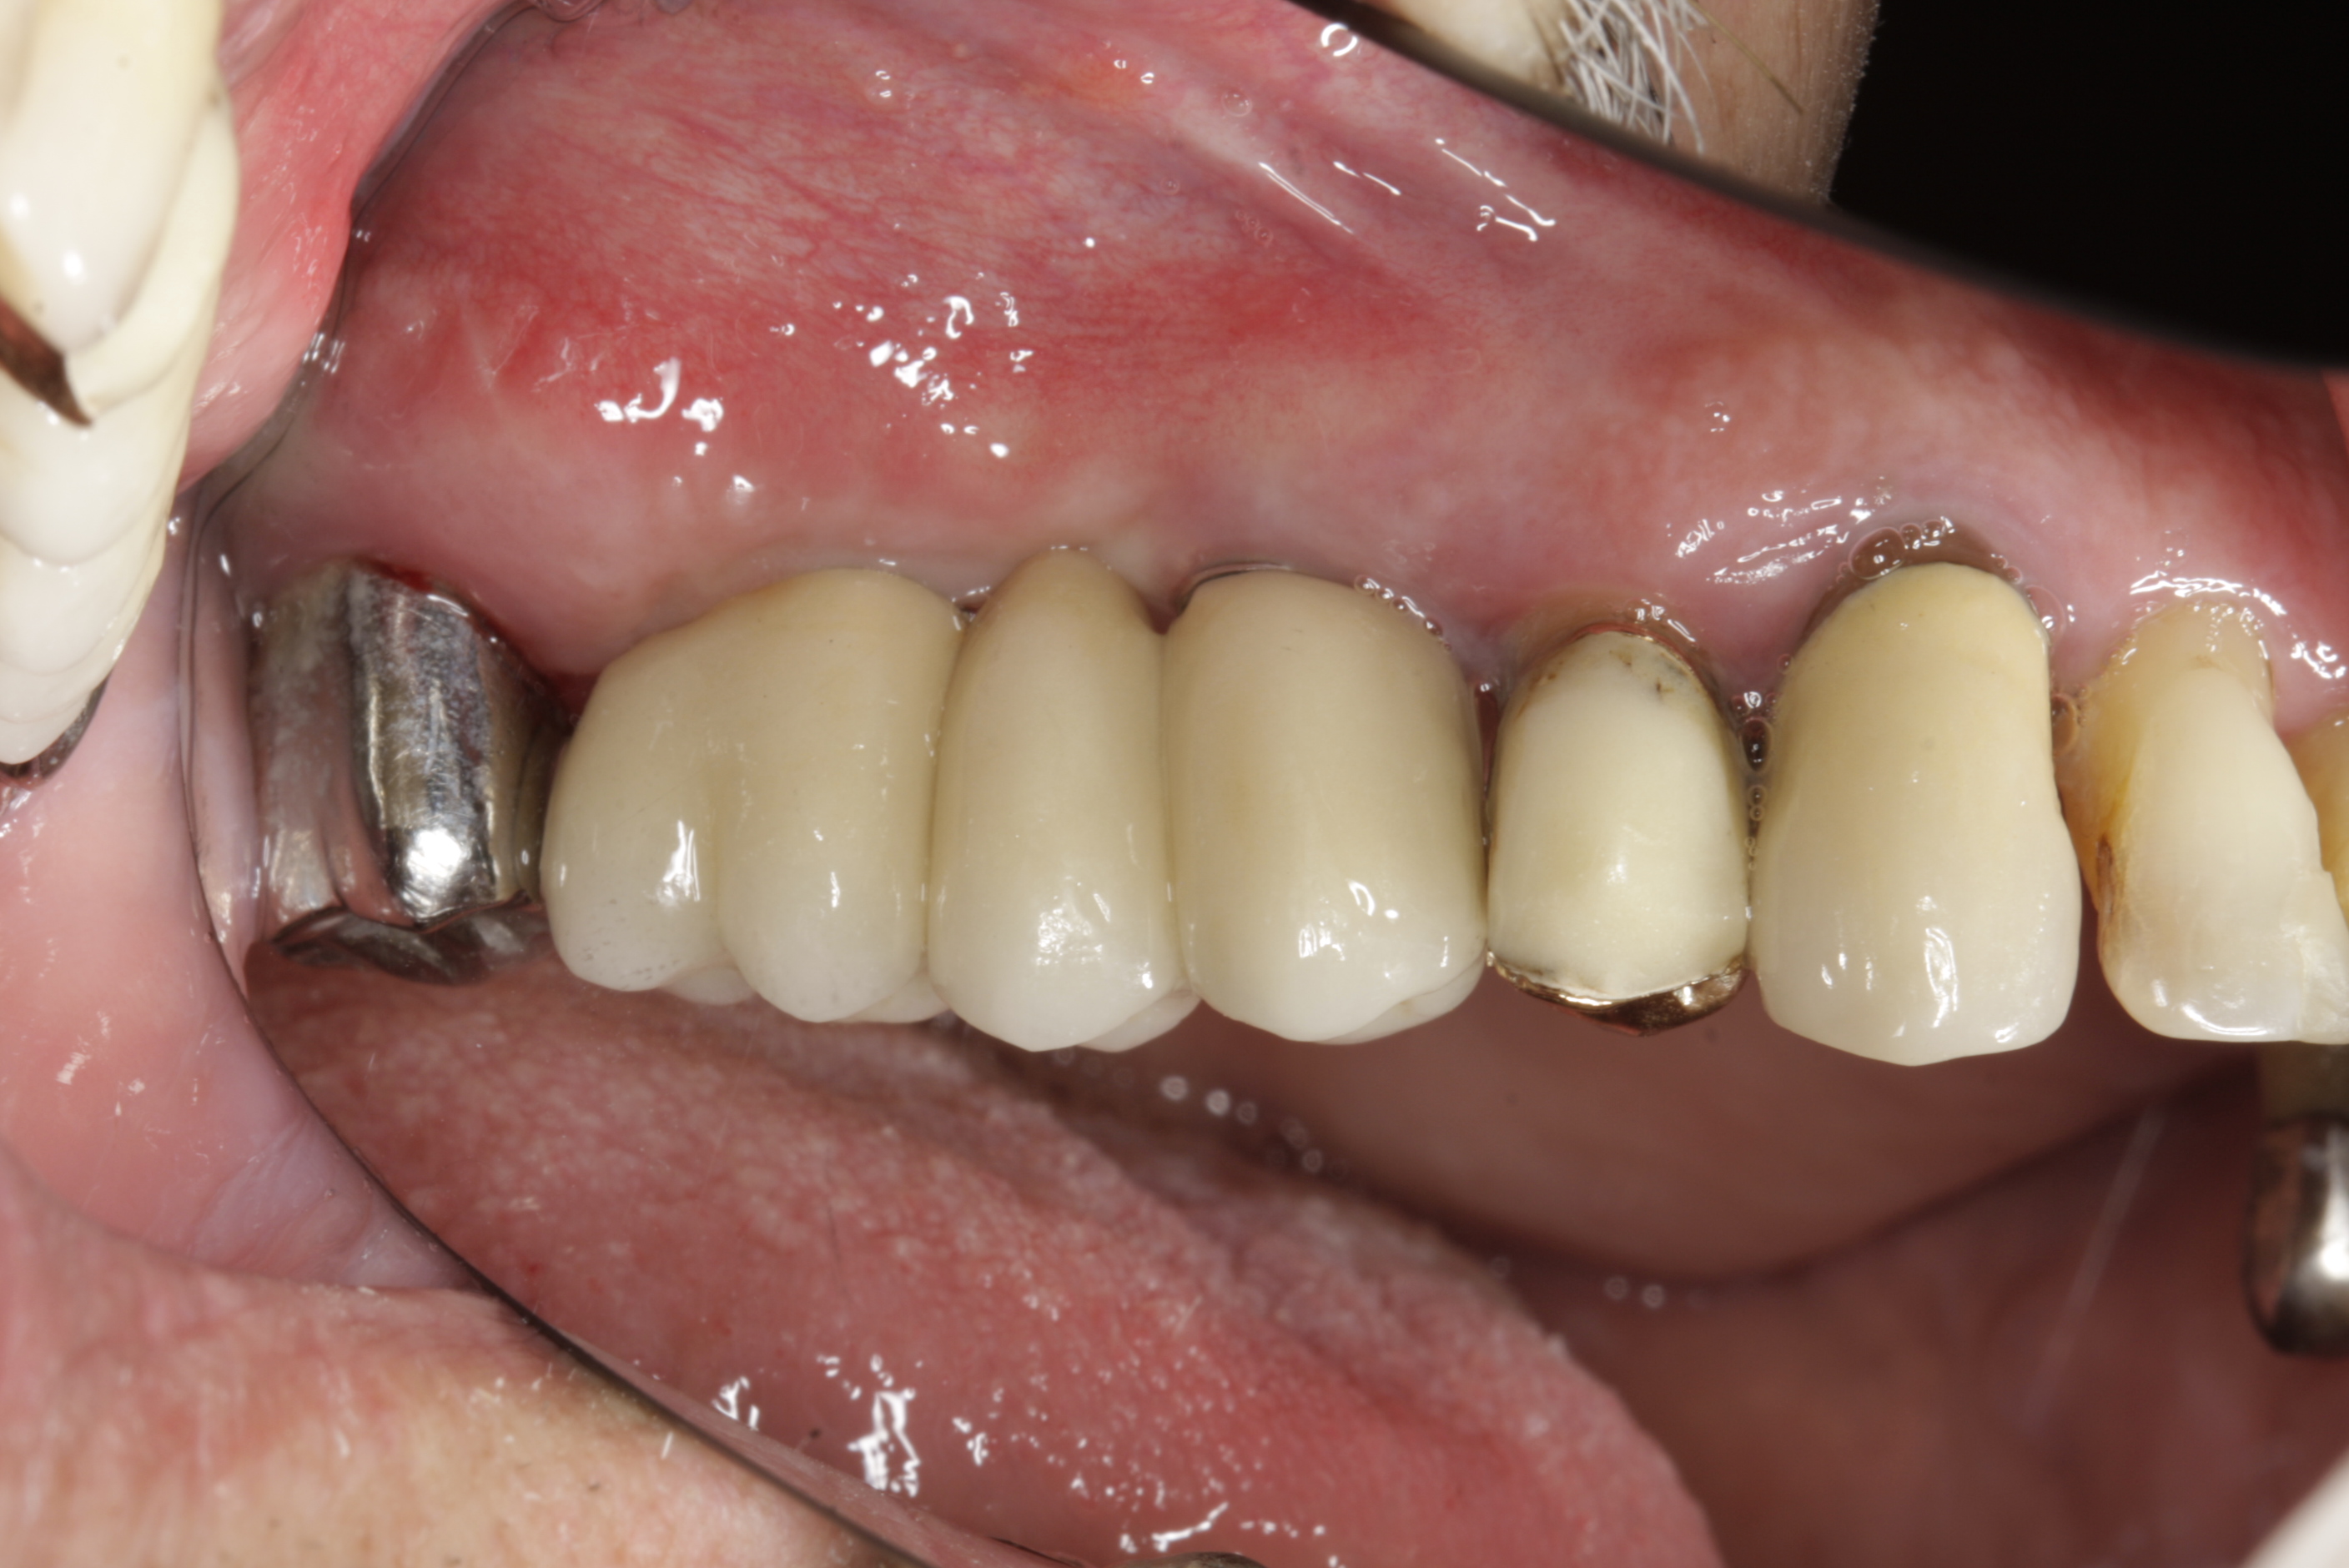

Protetické řešení může být pomocí můstku, který je kotvený na implantátech nebo pomocí jednotlivých korunek na implantátech.

V zásadě je možné do těchto můstků zařadit i přirozené zuby, zejména pokud je potřeba tyto zuby ošetřit proteticky – korunkami. Korunky nebo můstky mohou být na implantáty nacementovány nebo přišroubovány.

Zdravé zuby zůstanou zachovány a přitom náhrady jsou pevné, jako na vlastních zubech